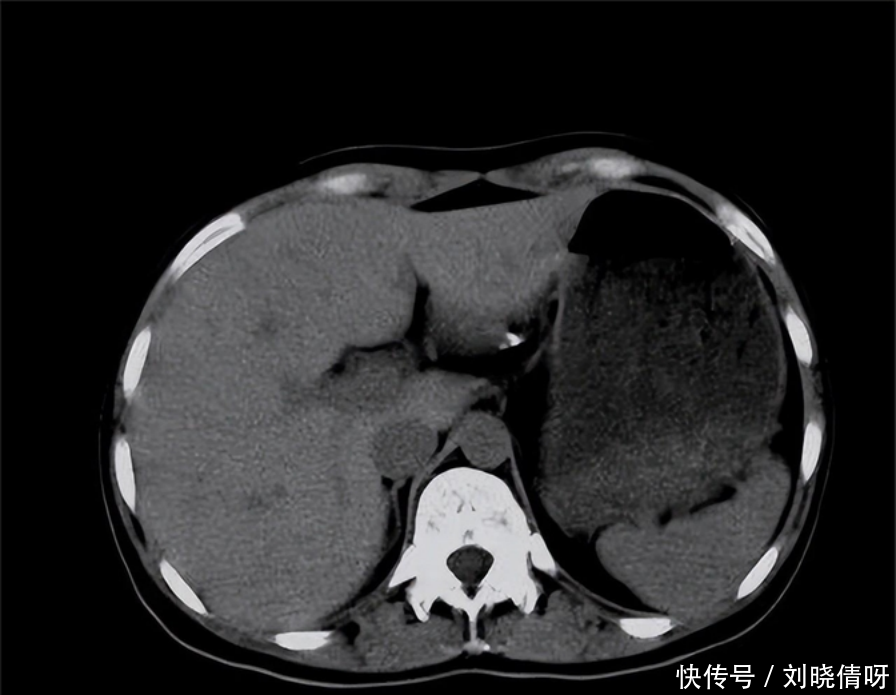

医生经过检查,发现张先生的腹部中间和左上腹有持续的疼痛,初步判断可能是胰腺炎。通过血液检查和X线检查,医生发现张先生的血清脂肪酶和血清淀粉酶水平升高,X线显示胰腺区域有钙化灶,确诊为急性胰腺炎。经过治疗,张先生的疼痛得到了缓解。

胰腺位于上腹部深处,隐藏在胃后,形状扁平,颜色灰红,分为头、颈、体、尾四个部分,重约75克。它不仅是人体第二大消化腺,还具有内分泌功能。外分泌腺分泌胰液,含有多种消化酶,帮助消化脂肪、糖和蛋白质。内分泌功能由胰岛细胞执行,主要分泌胰高血糖素、胰岛素、生长抑素和胰多肽,这些物质对人体的血糖平衡至关重要。

胰腺的健康对我们至关重要。胰腺炎的发病率随着生活水平的提高而上升,长期饮酒和暴饮暴食是导致胰腺炎的常见因素。胆道疾病,如胆结石和胆道感染,也可能引发胰腺炎。胰腺炎分为急性和慢性两种,急性胰腺炎症状严重,可能危及生命,而慢性胰腺炎则可能导致胰腺癌,这是一种难以发现且死亡率极高的疾病。